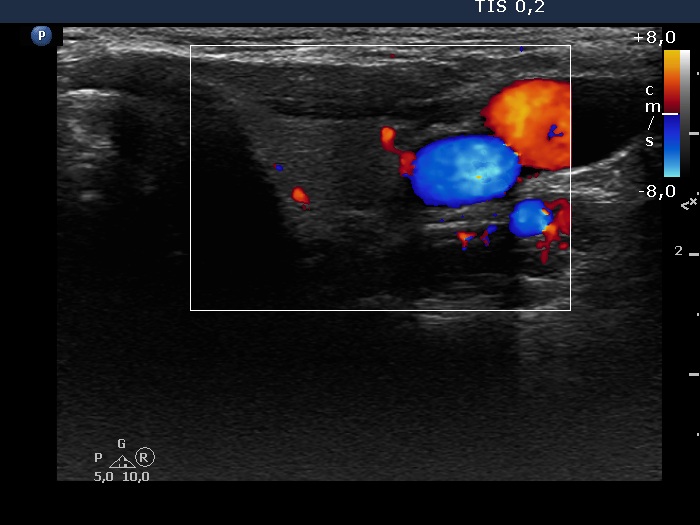

Discrete lesion or nodule in Hashimoto's thyroiditis - case 26 (1048)

Second examination three years later (ultrasonographic picture 7)

Left lobe, transverse scan, color Doppler mode. The vascularization has no relevance.